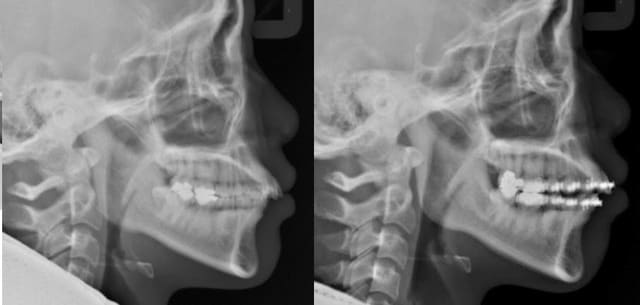

Et même, observez bien les deux panos l'une au dessus de l'autre ainsi les deux télés que j'ai superposées (par la technique des calques à demi transparents sur PSP). Vous verrez alors :

1 que sur les panos la différence de position des condyles n'est vraiment pas flagrante (c'est le moins qu'on puisse dire) !

2 que sur les télés il n'y a pas de remontée postérieure ni de recul de la mandibule comme ce serait la cas si effectivement il y avait eu repositionnement condylien, mais une simple ouverture mandibulaire.

L'origine de cette béance n'est donc pas liée à un problème de position condylienne, le prof de Seespan s'est complètement fourvoyé.